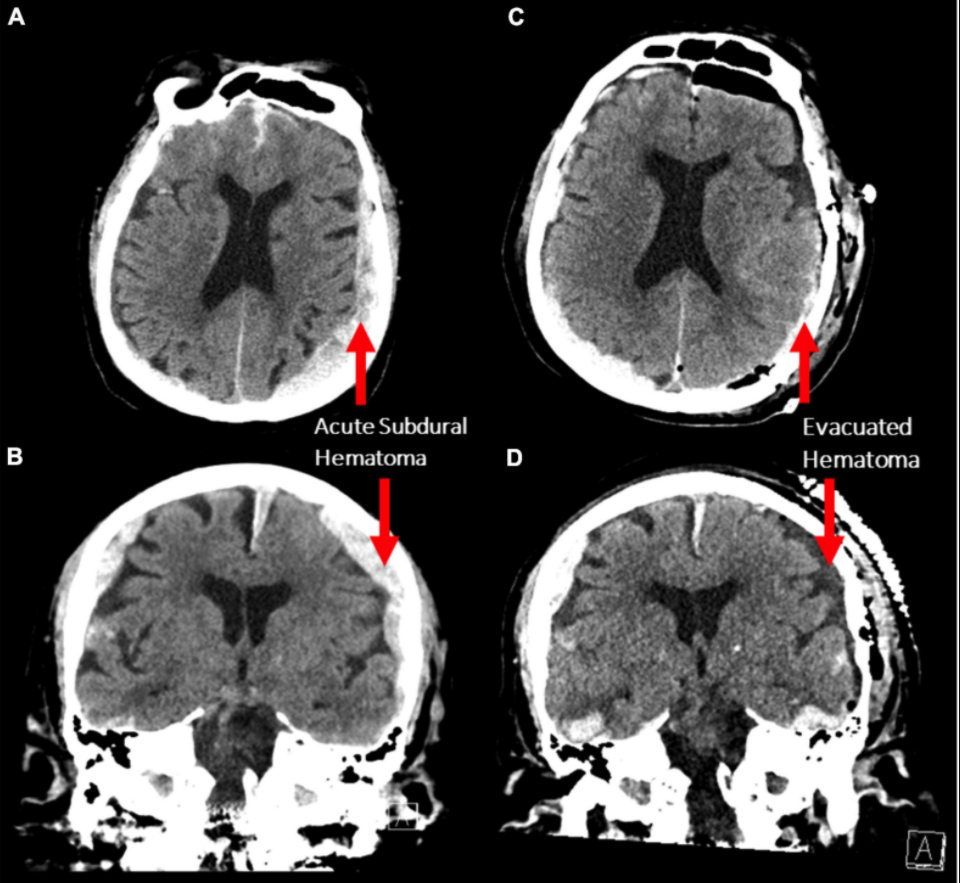

A study from the Department of neurosurgery, in Henan province, Zhengzhou China in 2022, analyzed the EEG recording from a dying human brain, obtained from an 87-year-old patient undergoing cardiac arrest after traumatic subdural hematoma. The report can be seen below:

“There were at least 12 identified electrographic seizures, after which a burst suppression pattern spontaneously developed over the left hemisphere (Figure 2A). Shortly thereafter, electrographic activity over both hemispheres demonstrated a burst suppression pattern, which was followed by development of ventricular tachycardia with apneustic respirations and clinical cardiorespiratory arrest.

What this shows was definite electrical activity in the brain for 10 minutes. The patient’s family informed doctors they ‘did not want to resuscitate’, all treatment stopped, and the patient passed away. That time, however brief, where the EEG resonated energy and electricity, may well have been that ‘near death’ hallucinatory experience that human beings have yearned to know since the dawn of humanity.